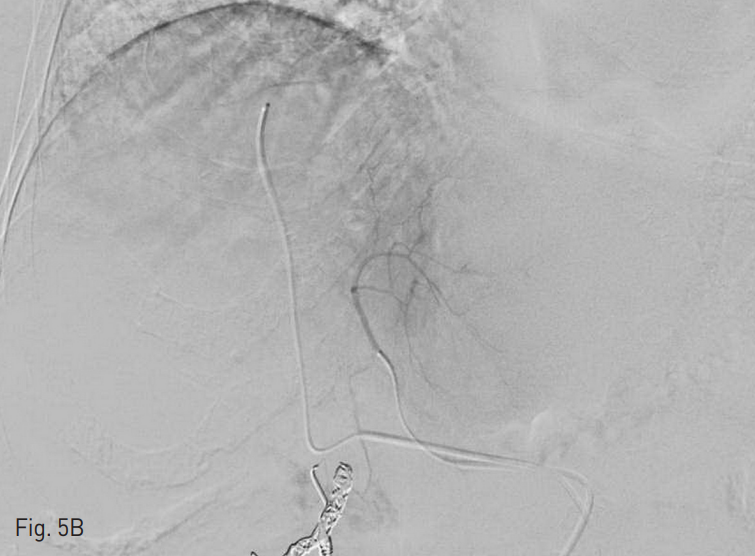

평가 후 1 주 후에 방사선색 전술을 시행하였다. 우측 총대퇴동맥에 4 Fr sheath 2개를 삽입한 뒤 4 Fr Yashiro catheter (Jung Sung Corp., Seoul, Korea) 2개를 이용하여 CT 간동맥 조영술을 시행 하였고 2.0 Fr microcatheter (Progreat, Terumo, Tokyo, Japan)를 이용하여 좌측 간동맥과 우측 간동맥을 각각 미세선택한 뒤 좌측 간동맥에 1GBq, 우측 간동맥에 0.3GBq에 해당하는 SIR-Spheres (Sirtex Medical Limited, Sydney, Australia)를 주입했다 (Fig. 5).

Fig. 5

90Y microspheres were infused into the tumor through the right hepatic artery (0.3G Bq) (A) and the left hepatic artery (1. 0G Bq) (B).